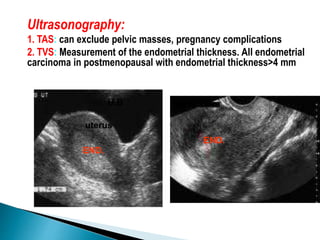

Ultrasonography:

1. TAS: can exclude pelvic masses, pregnancy complications

2. TVS: Measurement of the endometrial thickness. All endometrial

carcinoma in postmenopausal with endometrial thickness>4 mm

uterus

END.

U.B